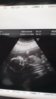

Rv 17+6 <3